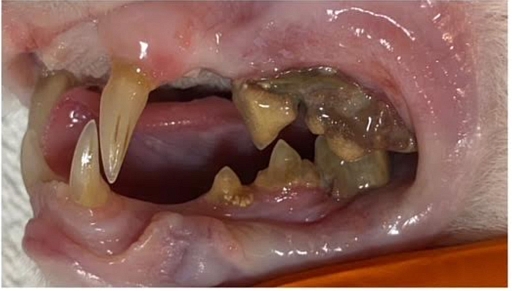

Die grösste Baustelle aber war und ist ihr Gebiss:

Bisher wurde eine Seite behandelt, einige Zähne sind dabei praktisch fast von alleine raus gefallen andere mussten gezogen werden.

Da ihr aufgrund ihres Alters keine zu lange Narkose zugemutet werden sollte, wurde erst eine Seite ihres Gebisses gemacht, die andere Seite folgt in einigen Wochen.

Bereits jetzt speichelt sie weniger und macht allgemein einen besseren Eindruck. Karisma hat vermutlich viele Jahre unter schlimmen Zahnschmerzen gelitten.